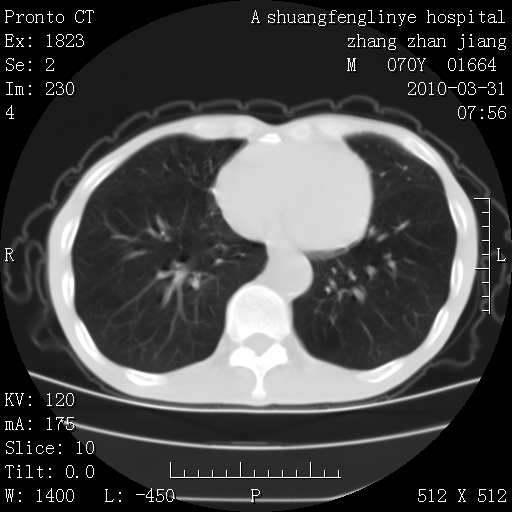

双上肺继发型tb并左上空洞形成,主动脉冠脉钙化。

1)两肺上叶继发性肺结核并左肺上叶空洞形成。2)冠状动脉及主动脉钙化。